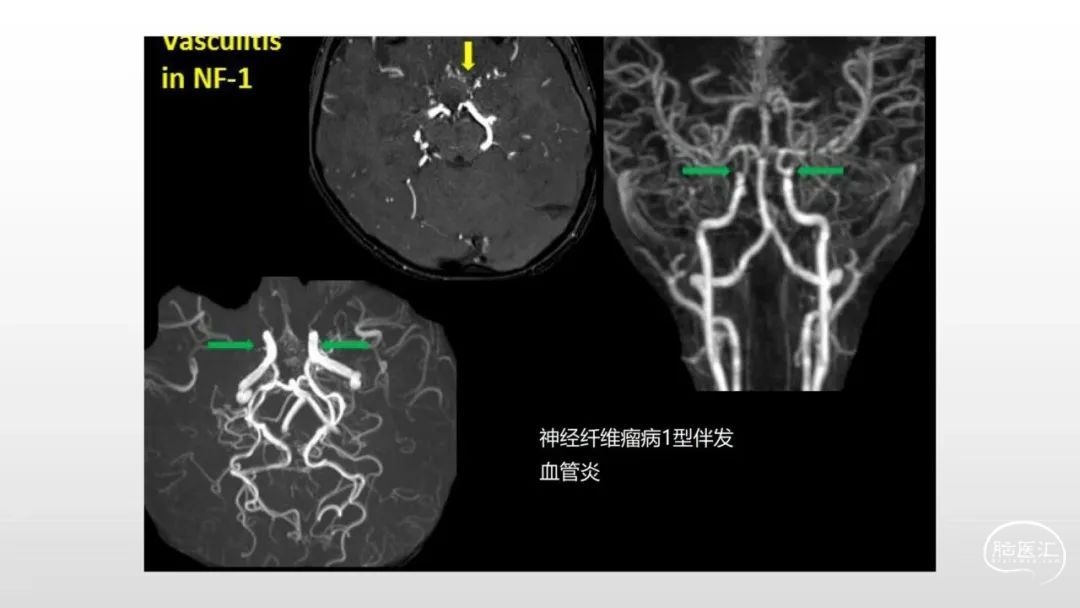

颅脑影像诊断基础知识讲座:感染和免疫性疾病2